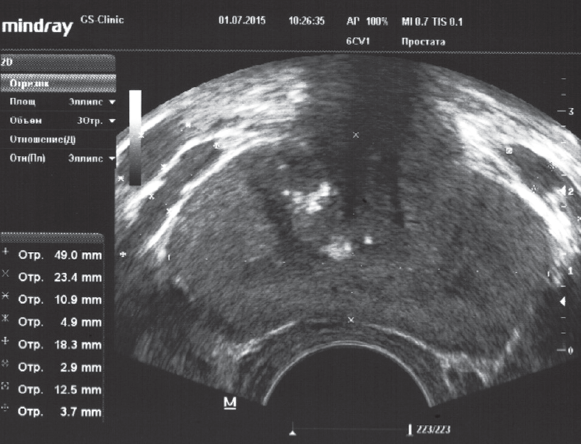

Как при Nutcracker syndrome, так и при синдроме Мея – Тюрнера отмечается венозное полнокровие простатического сплетения. При синдроме Мея – Тюрнера развивается, как правило, двустороннее варикоцеле, а по данным ТРУЗИ визуализируется билатеральное расширение вен простатического сплетения (рис. 7).

Рис. 7. ТРУЗИ простаты пациента К., 33 года, с двусторонним варикоцеле 3-й стадии при синдроме Мея – Тюрнера. Объем простаты — 22,3 см3. Максимальный диаметр вен слева —10,9 и 18,3 мм, справа — 12,5 мм. Хронический калькулезный простатит

Fig. 7. Transrectal ultrasound imaging of the prostate of patient K., 33 years old, with bilateral stage 3 varicocele and May–Thurner syndrome. Prostate volume – 22.3 cm3 . The maximum diameter of the veins on the left is 10.9 and 18.3 mm, on the right – 12.5 mm. Chronic calculous prostatitis